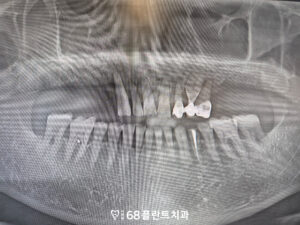

◆ 전 > 후 ◆

치료 마무리 후 사진입니다.

환자분께서는 어금니의 상실로 인해

앞니로만 식사를 하다보니 많이 불편해하셨으나

본원에서의 치료를 통해 식사도 편해지고

일상생활도 편안해져 만족해 주셨습니다.